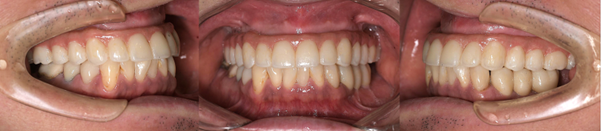

After

インプラント症例1 治療後

治療後の状況

無事に結婚式までに治療を終えることができました。見た目が大幅に改善されたこと、入れ歯に比べて噛みやすく、脱離もしないことを大変喜んでいただきました。インプラント周囲炎予防の為、患者様には口腔内清掃を毎日頑張ってもらっています。それから1〜3か月ごとにプロフェッショナルケアを行っています。

治療の注意事項

睡眠時の歯ぎしりや日中のくいしばりがあると、気づかないうちに歯やインプラントへ過剰な力がかかります。継続して歯や歯ぐきの状況を確認していくことが重要です。

インプラント症例2 治療後

見違えるほど見た目が改善されたことを大変喜んでいただきました。患者様は大変モチベーションが高く、口腔内清掃を毎日頑張ってされています。それから1〜3か月ごとのメンテナンスには欠かさず来てくださっています。